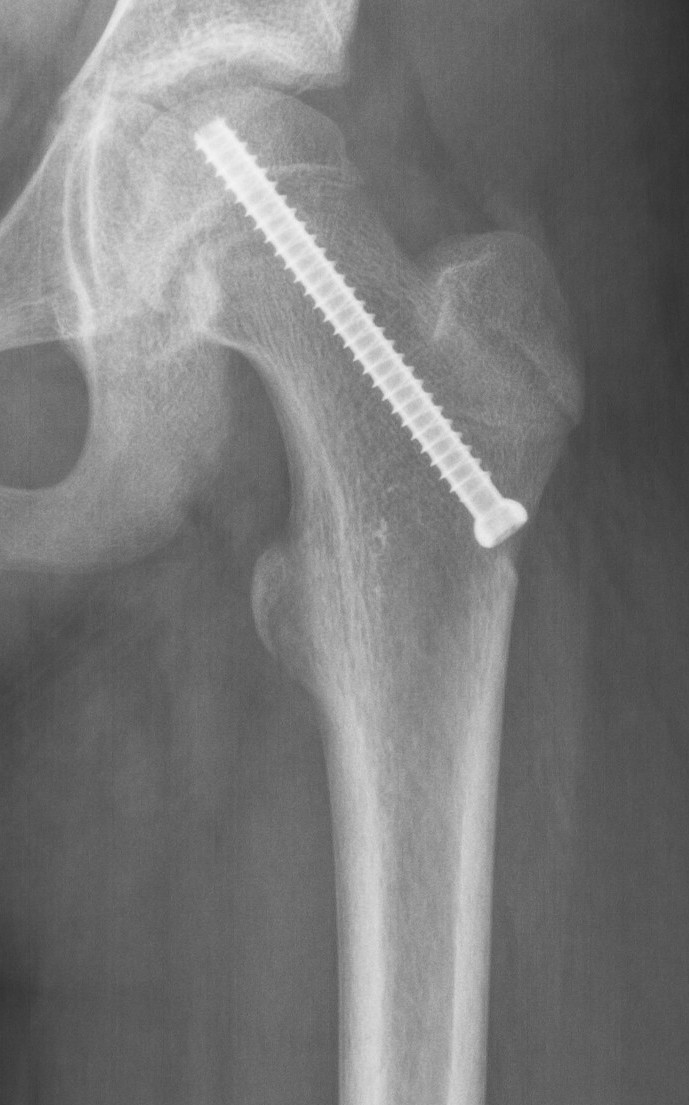

Reisiluun pään liukuma hoidetaan leikkauksella, jossa liukuma kiinnitetään ruuvin avulla estämään siirtymän lisääntymisen. Leikkaushoidon tavoitteena on kiinnittää reisiluun pään siirtymä ja ehkäistä lonkan toimintahäiriöitä ja kulumista. Suuriasteinen reisiluun pään liukuma edellyttää reisiluun yläosan katkaisuleikkausta.